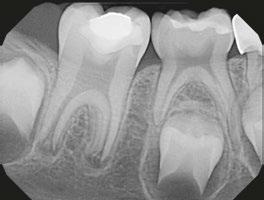

Figures 1 and 2: Example of staining from traditional MTA, non-vital bleaching after Figure 3: Pre-op Figures 4 and 5: Pulp cap Figures 6: Apexogenesis

Figure 1: Occlusal films at recall visit in high caries risk patients showing loss of material and recurrent decay in composite resin strip crowns Figure